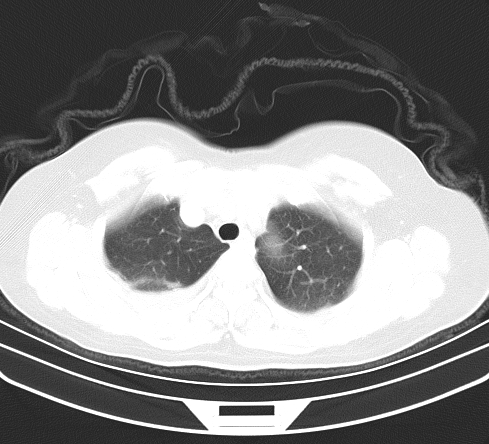

以下是引用余辉在2009-2-19 20:10:00的发言:[br]多考虑急性感染性病变,右中叶尚可见多枚小斑片状影,多为化脓性肺炎,双侧胸腔积液

以下是引用随光逐影在2009-2-19 20:33:00的发言:[br]1)考虑右肺炎症;建议抗炎治疗后复查。2)双侧胸腔积液(以右侧为甚)。

以下是引用花凤凰在2009-2-19 20:46:00的发言:[br]病人有发热,胸痛急性起病,主要病变位于右肺中叶外侧段,呈楔行改变,位于外带胸膜下,考虑为肺梗塞可能!!!!!!!!!!!!!!!!!!!!!!!!!!!!!!!!!!!